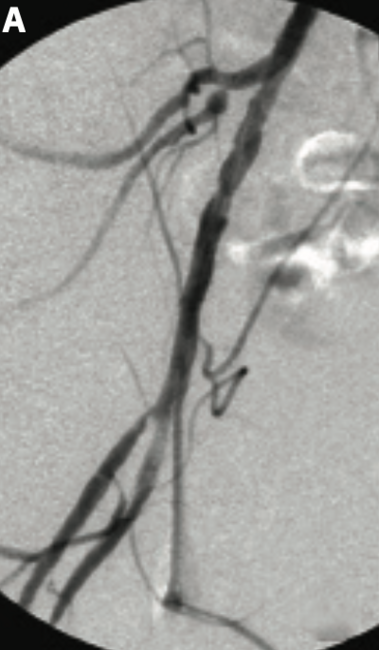

Working in an outpatient endovascular center, also known as an office-based lab (OBL), prompts certain considerations that do not exist in a hospital setting. The most important consideration is that there is no immediate availability of an operating room, anesthesiology team, blood bank, code team, or any other subspecialists that may be needed in an emergency such as a procedural complication or patient decompensation. It is therefore incumbent upon those of us operating in an outpatient center to take additional precautions to both try to avoid complications and to promptly treat complications when they do occur. Failure to rapidly resolve complications may mean an unsatisfactory patient outcome or even death. If the problem cannot be managed on site, then an inter-institutional transfer may become necessary. A transfer requires that the patient is stable enough for transport and that a relationship exists between the outpatient center and a hospital and/or accepting physician(s) with the necessary skills to treat the problem. If the physician working in the OBL also maintains privileges at the receiving hospital, the transfer process may be smoother. In other cases, the local hospital may not have the expertise to resolve the problem and may only be able to stabilize the patient, with subsequent transfer to a more remote institution for definitive treatment. This latter situation describes my OBL, and I have consequently worked to put procedures and practices into place to try to prevent or mitigate patient complications.